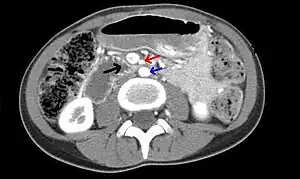

| Abdominal and pelvic computed tomography scan showing duodenal compression (black arrow) by the superior mesenteric artery (red arrow) and the abdominal aorta (blue arrow). | |

Diagnosis is can be difficult, and usually one of exclusion. SMA syndrome is generally considered only after people have undergone an extensive evaluation of their gastrointestinal tract including upper endoscopy, and evaluation for various malabsorptive, ulcerative and inflammatory instestinal conditions with a higher diagnostic frequency. Diagnosis may follow X-ray examination revealing duodenal dilation followed by abrupt constriction proximal to the overlying SMA, as well as a delay in transit of four to six hours through the gastroduodenal region. Standard diagnostic exams include abdominal and pelvic computed tomography (CT) scan with oral and IV contrast, upper gastrointestinal series (UGI), and, for equivocal cases, hypotonic duodenography. In addition, vascular imaging studies such as ultrasound and contrast angiography may be used to indicate increased bloodflow velocity through the SMA or a narrowed SMA angle.[13][14]

It is typically caused by an angle of 6°–25° between the AA and the SMA, in comparison to the normal range of 38°–56°, due to a lack of retroperitoneal and visceral fat (mesenteric fat). In addition, the aortomesenteric distance is 2–8 millimeters, as opposed to the typical 10–20.[15] However, a narrow SMA angle alone is not enough to make a diagnosis, because people can have a narrow SMA angle with no symptoms of SMA syndrome.[16]